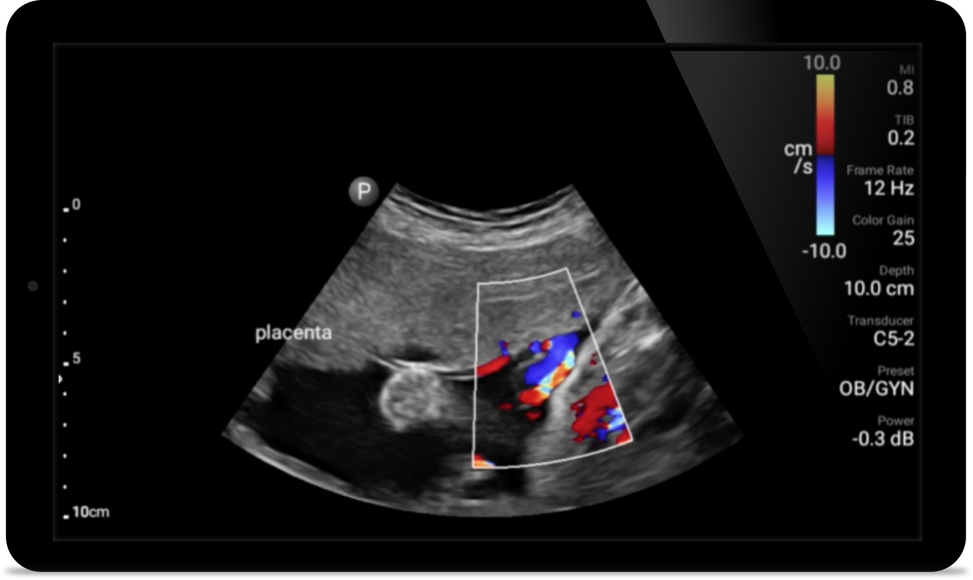

• 4 to 1 MHz extended operating frequency range • 2D, color Doppler, M-mode, advanced XRES and multivariate harmonic imaging • High-resolution imaging for abdominal and cardiac applications: Cardiac, OB/GYN, Lung, Abdomen and FAST imaging preset optimizations Lumify aids life-saving technology in prehospital setting